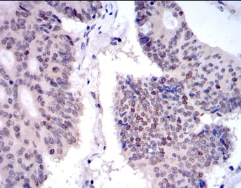

IHC    1/200 - 1/1000